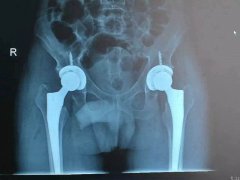

近日,我院骨科成功為一名老年男性患者實(shí)施雙側(cè)股骨頭無(wú)菌性壞死人工髖關(guān)節(jié)小切口DA……